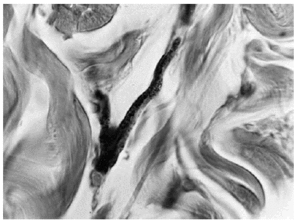

Presentaba una mácula hiperpigmentada de coloración azul-violácea y aspecto moteado que abarcaba la región interescapular. La lesión tenía unos bordes uniformes y bien delimitados (fig. 1). El resto de la exploración dermatológica no ofrecía ninguna otra lesión de interés. Se procedió a la realización de una biopsia cutánea que reveló una epidermis y una dermis normales salvo por la presencia en dermis reticular de células ovaladas, fusiformes y alargadas con intensa pigmentación melánica y algunas ramificaciones (figs. 2 y 3). Se efectuó una tinción con rojo Congo que resultó negativa. Las tinciones inmunohistoquímicas para proteína S100 y HMB 45 demostraron positividad de esas células. En la microscopia electrónica se pudo confirmar la presencia de melanocitos dérmicos. Debido a las dificultades para desparafinar la pieza no fue posible determinar la presencia de vaina extracelular melanocítica debido a la deficiente calidad de las imágenes.

Fig. 3. Detalle de los melanocitos dérmicos.